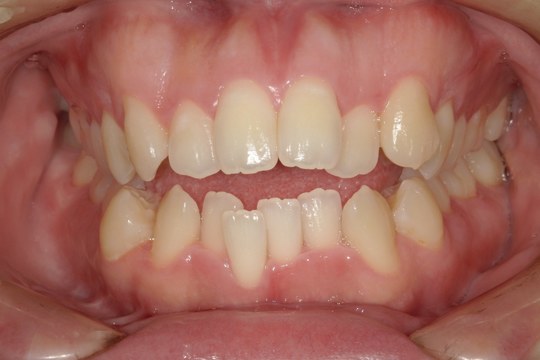

Before

浜松市中央区・自動車学校前駅のインビザラインの症例

N.T 20代女性

上の前歯が出ているのが気になる、左下の第二小臼歯が内側に入っているのが気になるとの主訴でご来院。

上の前歯を下げて左下の第二小臼歯を外に移動させることで気になっていた上顎前突を改善しました。

治療の期間:R4. 4/22〜R6. 11/2

治療の価格:66万円